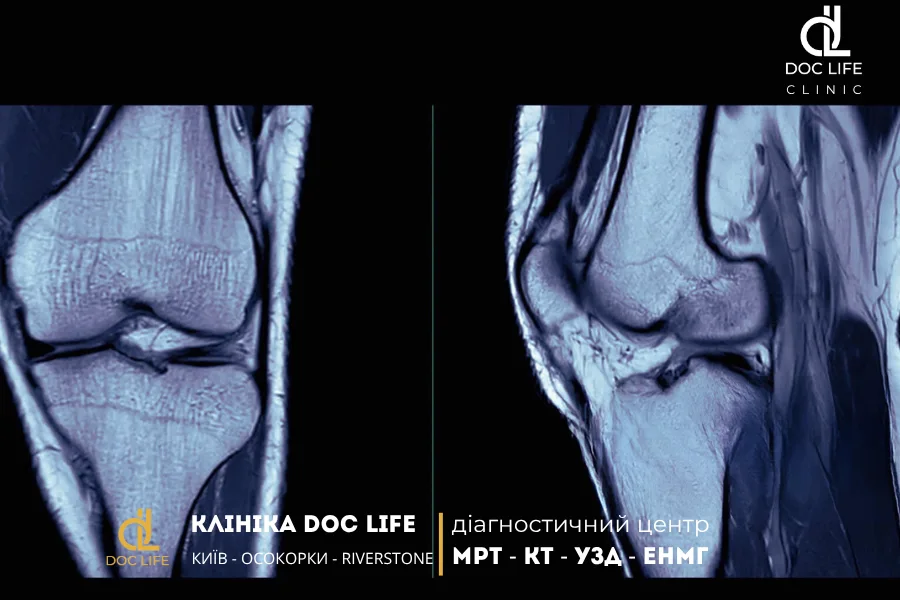

МРТ колінного суглоба: травми, розриви та артроз

На зображеннях МРТ коліна чітко видно товщину зв’язок, місце їхнього прикріплення та наявність набряку навколо. Все це допомагає ортопеду оцінити ступінь пошкодження й вирішити, чи потрібно оперативне лікування.

МРТ колінного суглоба дозволяє побачити навіть найдрібніші розриви, які не завжди видно при артроскопії або УЗД. Магнітно-резонансна томографія визначає форму, глибину, напрям і давність ушкодження, а також оцінює, чи є ознаки дегенерації тканини меніска. Це допомагає лікарю прийняти рішення: проводити операцію чи обмежитися консервативною терапією та фізіопроцедурами.